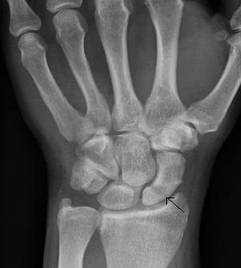

Unfortunately scaphoid fractures do not always show on an initial xray; they may not show up until the initial pain has settled down. The following patient's fracture did not show up on the original xrays taken in the A&E department. An MR scan shows the fracture clearly; the blue arrow points to the white area in the scaphoid that represents bruising in the bone. The subsequent xray confrims the presence of the fracture, albeit still very subtly (white arrows).

Most scaphoid fractures will heal in a plaster cast. Some however have an increased risk of not healing, and we have a low threshold for fixing these early. In the initial stages it is possible to do this with a minimal incision (percutaneous fixation). This fracture is at the lower end of the scaphoid (proximal pole fracture). We would aim to fix this early.